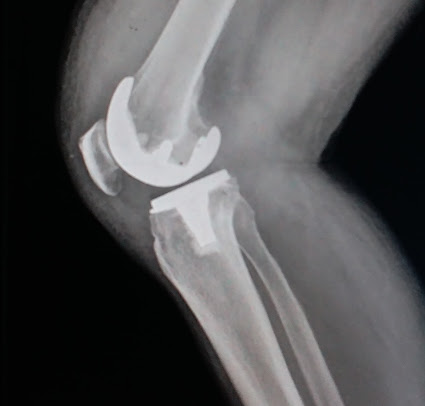

Hospital Gallery

The Veer Hospital is committed to providing affordable, quality health care to patients by incorporating improvement in its day-to-day schedule.